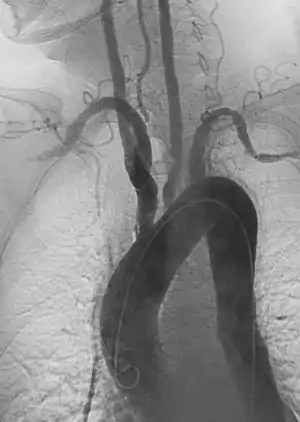

- Endovascular aneurysm repair: Placement of endovascular stent-graft across an aneurysm to prevent expansion or progression of the defective vessel.[6]

- Aortic aneurysms include thoracic, abdominal or thoracoabdominal. Treatment strategies are customized depending on the location, size, rate of growth and extent of the aneurysm as well as the medical comorbidities of the patient. For example, an intact, small but slowly growing aneurysm may be safely monitored with serial imaging for months or years before elective repair is considered. Elective endovascular aortic grafting is now routinely attempted when possible. Endovascular aortic repair (EVAR) refers to treatment of an abdominal aortic aneurysm, while thoracic endovascular aortic repair (TEVAR) is performed on the thoracic aorta. A ruptured aneurysm may be taken emergently for open, endovascular or combination repair.

A variety of endovascular grafts are available, and each has advantages and disadvantages depending on the characteristics of the aneurysm and patient.[89]